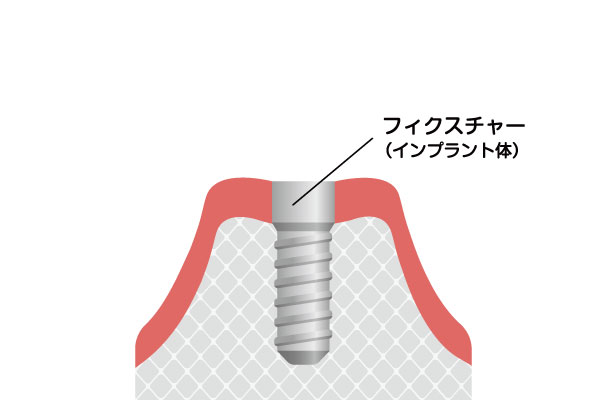

インプラントとは、歯を失った部分の顎の骨にチタン製の人工歯根を埋め込み、その上に被せ物を装着する治療法です。数十年の歴史と確かなエビデンスがあり、骨とインプラントが強固に結合(オッセオインテグレーション)することで、自分の歯のようにしっかりと噛めるようになります。入れ歯のようにガタつくこともなく、見た目も天然歯と遜色ないため、心からの笑顔と食事の楽しみを取り戻すことができます。

一次手術

インプラント(人工歯根)の埋入

一次手術